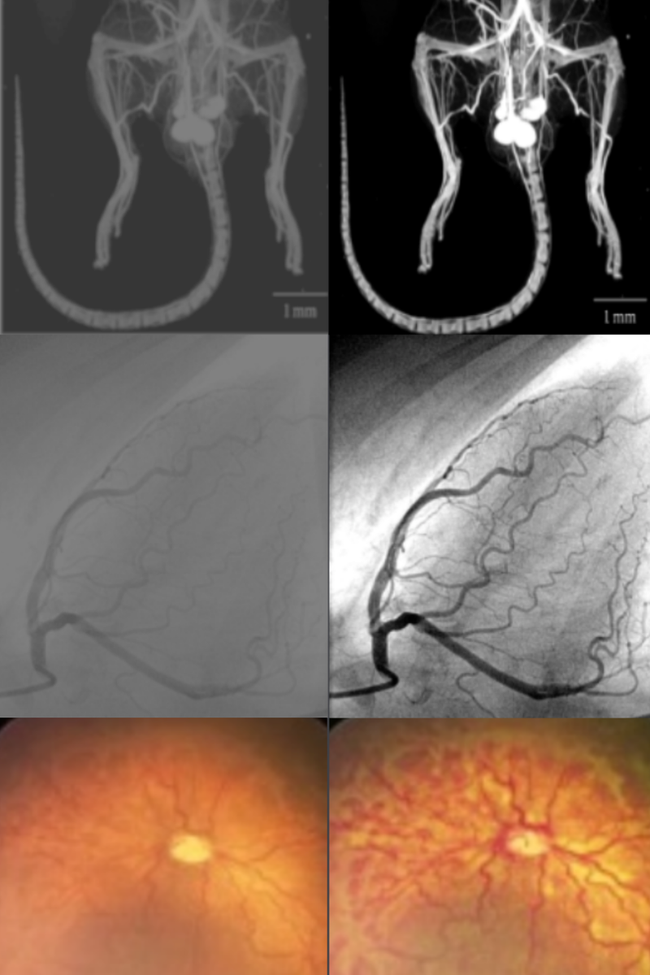

Healthcare is one of the industries benefiting the most from computer vision applications. Common use cases are:

AI-driven diagnostic imaging for enhanced accuracy and improved patient outcomes

Early detection of diseases like cancer

Automated analysis of medical scans (X-rays, MRIs, CT scans)

Remote patient monitoring for the elderly and those with chronic conditions

Some AI systems have achieved up to 95% accuracy in detecting cancer, leading to earlier interventions and better outcomes.